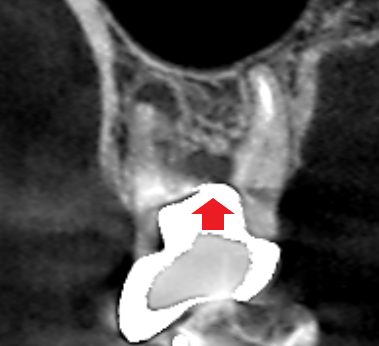

6カ月後の経過観察時の冠状断のCT画像です。適切なパーフォレーションリペアによって根の分岐部にあった膿の影が消え、歯槽骨が再生しています。

適切な精密根管治療により、近心頬側根と根の分岐部にあった両方の膿が改善しました。両方の膿が同時に良くならなければ手術や分割抜歯を行わなければいけなせん。根管治療は、できるだけ手術や分割抜歯をせずに治すのが当医院の方針です。今回も低侵襲の根管治療により患者さんの負担を最小限にして治すことができました。